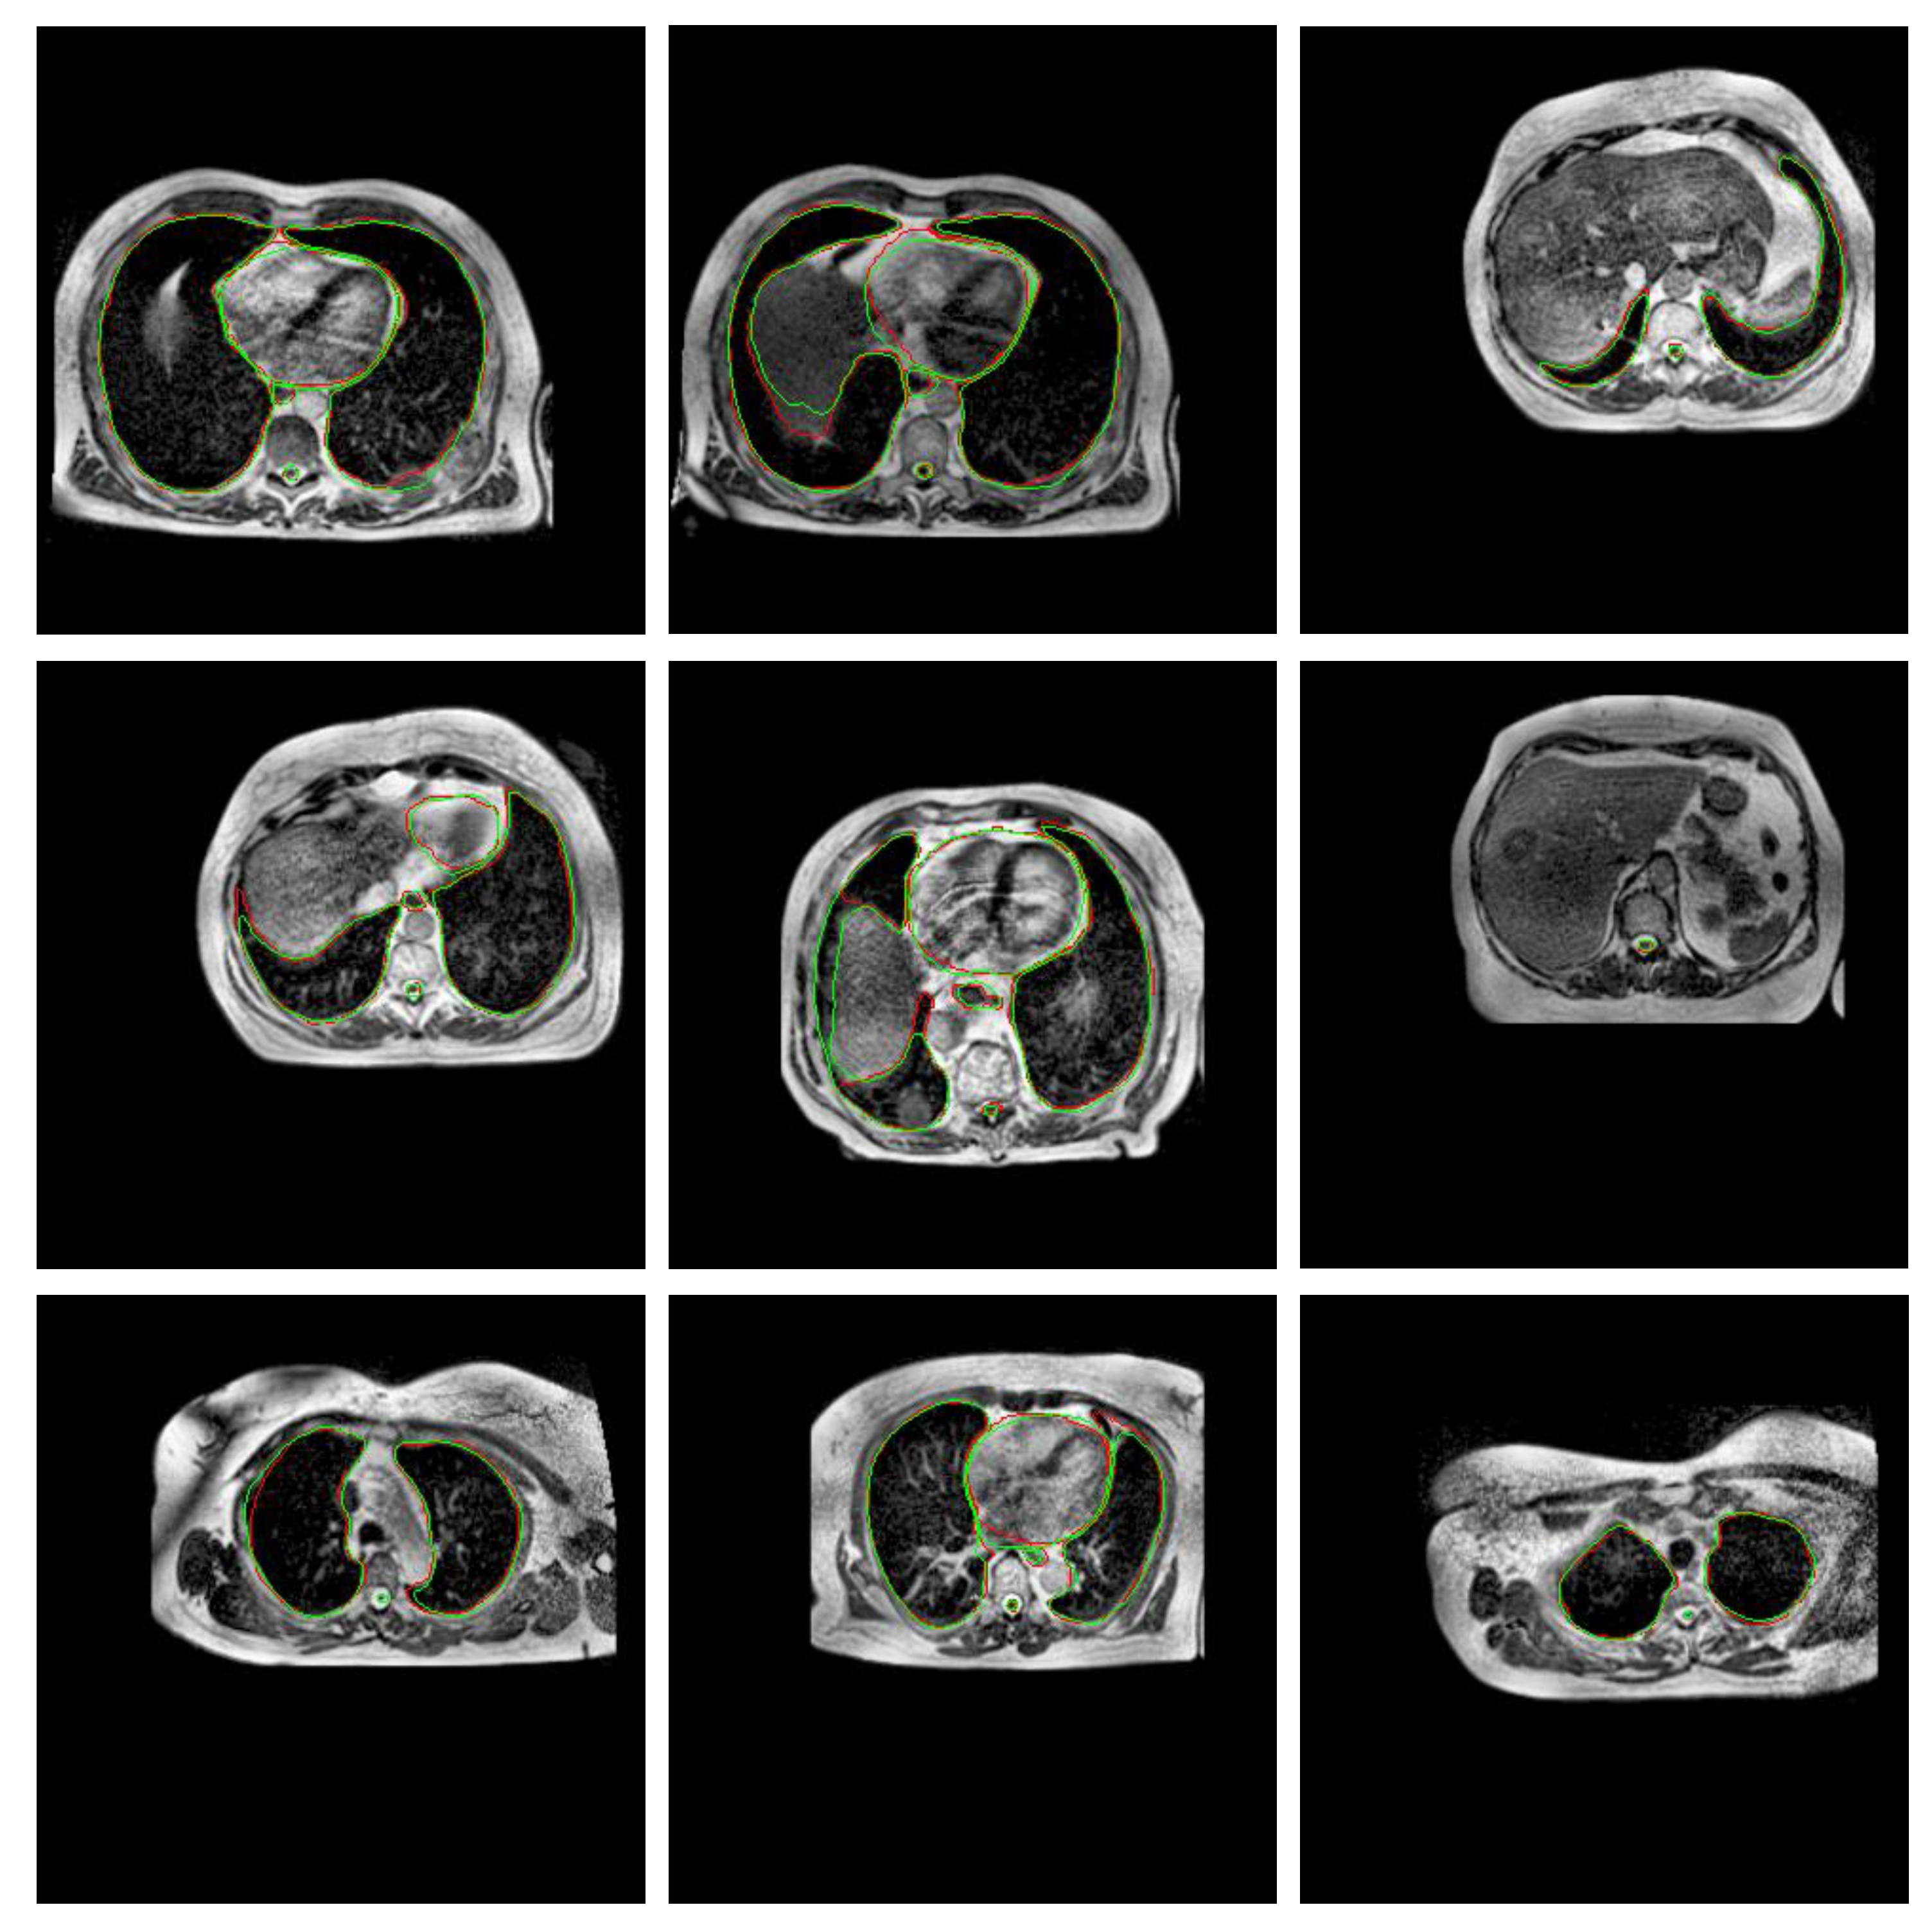

3.1. Experiment 1: Model Selection

| Model | DSC | IoU | HD (mm) | # Parameters | Training Time | Inference Time |

|---|---|---|---|---|---|---|

| Efficient-UNet | 0.804 ± 0.058 | 0.711 ± 0.062 | 25.663 ±18.724 | 20,225,550 | 4 h | 3.71 s |

| UNet | 0.761 ± 0.078 | 0.657 ± 0.086 | 35.915 ± 13.632 | 30,106,806 | 3.9 h | 7.07 s |

| ResAtt UNet | 0.677 ± 0.105 | 0.561 ± 0.115 | 21.536 ± 8.803 | 34,877,746 | 13.9 h | 5.37 s |